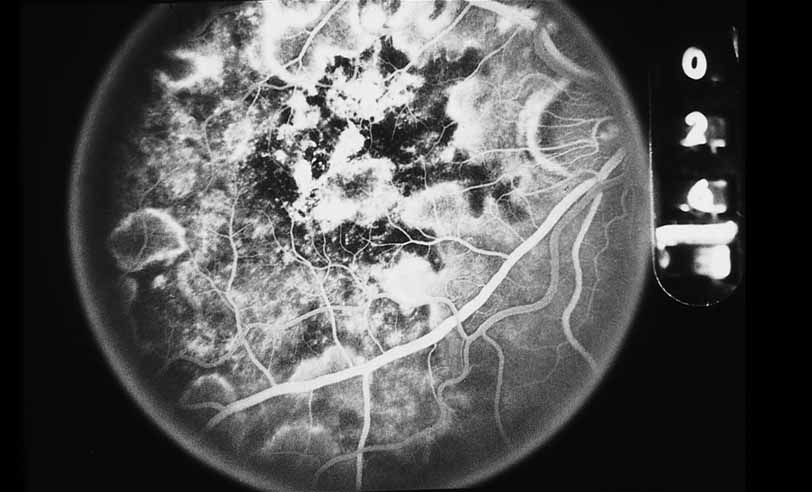

A third instance in which fluorescein angiography concentrating on the optic nerve may be helpful is in eyes with vascular engorgement of the optic nerve, especially with media opacities. Fluorescein angiography may help the clinician distinguish abnormally leaking capillaries from neovascularization. In acute multifocal hemorrhagic retinal vasculitis, optic nerve involvement is common in the early stages of the disease, 47 with optic nerve disc neovascularization seen later (see Figs. 10, 11, 12, and 13). Another fluorescein angiographic clue to the distinction between optic disc vessel engorgement and true neovascularization is the presence of associated large zones of retinal capillary nonperfusion such as those seen in sarcoidosis (see Figs. 14 and 15),34–40 acute multifocal hemorrhagic retinal vasculitis (see Figs. 10 and 11),47 or Eale disease (see Figs. 16 and 17).48–52

Fig. 10 Acute multifocal hemorrhagic retinal vasculitis. A middle-aged man presented with the picture of multiple branch vein obstructions and low-grade intraocular inflammation.

Fig. 11 Acute multifocal hemorrhagic retinal vasculitis. Fluorescein angiogram confirms the presence of associated retinal capillary non-perfusion without neovascularization at the onset of the disease.

Fig. 12 Acute multifocal hemorrhagic retinal vasculitis. The patient later developed disk neovascularization with vitreous hemorrhage. Note the areas of neovascular leakage from the optic nerve.

Fig. 13 Acute multifocal hemorrhagic retinal vasculitis. The patient underwent scatter laser photocoagulation to the zones of retinal capillary nonperfusion, which resulted in regression of the neovascularization.